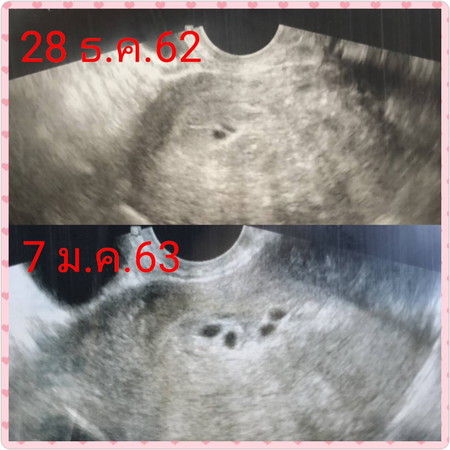

ไปอัลตร้าซาวน์มาวันนี้ค่ะ แม่ๆท่านใดเคยซาวน์ แล้วพบถุงตั้งครรภ์แบบนี้ไหมคะ (หมอบอก อายุครรภ์ประมาณ 1 เดือนคะ) ประจำเดือนครั้งสุดท้าย มาวันแรก 25 พ.ย.62 ค่ะ รบกวนแม่ๆด้วยนะคะ?

ว้าวว 😊😊😊 แฝดรึป่าวค่ะแม่ ลุ้นตามเลยค่ะ ที่เห็น เหมือนจะแฝดสี่เลยค่ะ แม่มาอัพเดตด้วยนะคะ

น่าจะเปนแฝดน่ะค่ะคุนแม่เพราะบ้านนี้ท้องแฝดซาวครั้งแรกก้อเจอถุงแบบนี้จร้า...ยินดีด้วยเรยแฝดสี่เรย

ของเราไปซาวมาวันนี้..คุณหมอบอกว่าเจอแต่ถุงตั้งครรภ์..ยังไม่เจอตัวเด็ก..คุณหมอบอกว่ามีความเสี่ยงท้องนอกมดลูกค่ะ..กังวลมากเลย.. คุณหมอบอก5weekแล้ว..ประจำเดือนมาครั้งสุดท้าย30พฤษจิกายน..แม่เจอตัวเด็กยังค่ะ